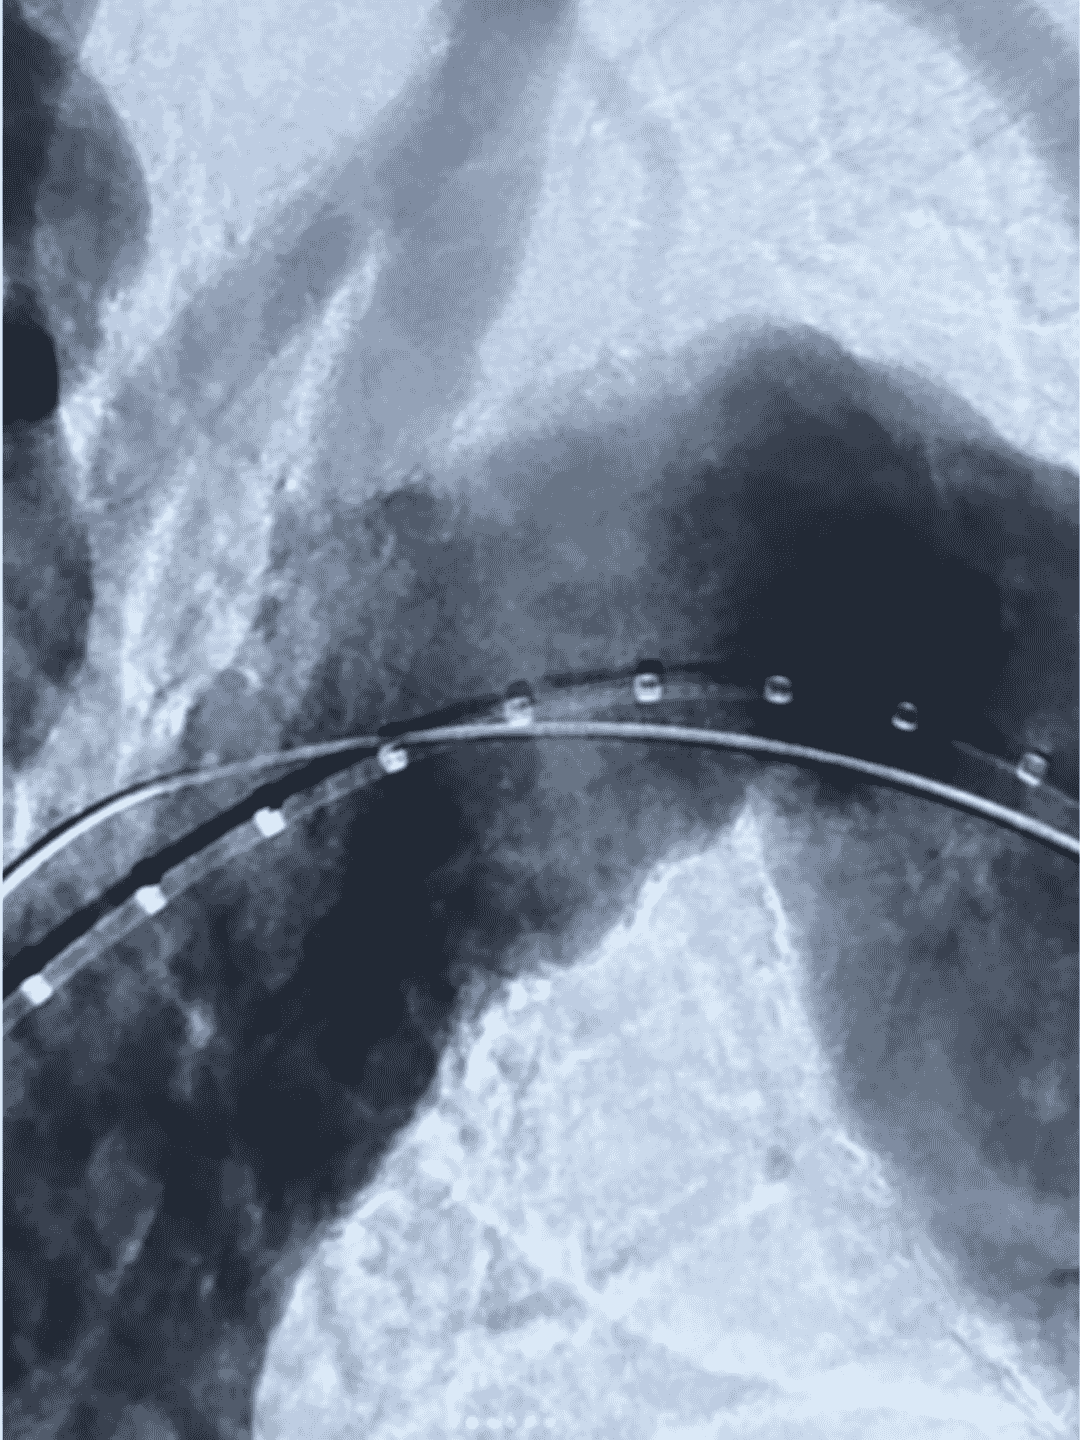

O Ankura™ Stent Graft representa o que há de mais avançado em reparo endovascular de aneurismas e dissecções da aorta — uma verdadeira combinação de tecnologia, segurança e performance clínica.

O sistema Ankura possui versões para aneurismas da aorta abdominal (AAA) e torácica (TAA), sendo indicado para reparo endovascular minimamente invasivo dessas patologias. A versão TAA também pode ser usada em dissecções torácicas

Dispõe de mecanismo tip‑capture, com barbelaos (6 no total na versão AAA) que asseguram ancoragem firme à parede vascular. Além disso, o design em nitinol autoexpansível fornece força radial estável para manter a posição do dispositivo

O sistema apresenta revestimento duplo em e‑PTFE sem suturas no corpo principal, o que reduz o risco de endoleak tipo IV. Na versão torácica, o selo proximal com a tecnologia “MINI Wave” otimiza o contato vascular, minimizando endoleaks e migracão